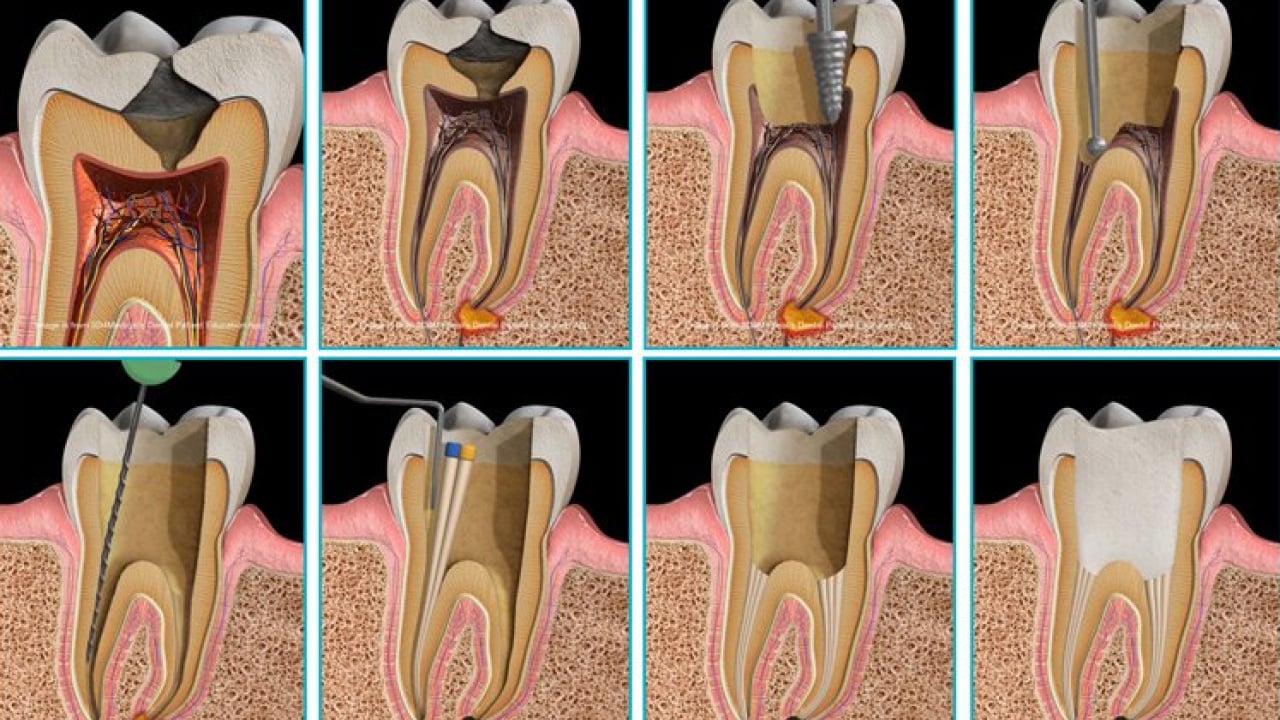

Dr. Öğr. Üyesi Sezer, "Dişin kök kanallarındaki sinir ve damar dokusu temizlenir, kanal duvarları arındırılır ve uygun materyallerle doldurularak diş restore edilir. Geçmeyen zonklayıcı ağrılar, gece uykudan uyandıran şiddetli ağrı, yüzde şişlik oluşturan apse, yemek yerken sıcakla veya dişe bastırınca oluşan hassasiyet gibi durumlar kanal tedavisi gerekliliğini düşündürür" diye konuştu.

“TEDAVİ SÜRECİ” Kanal tedavisi genellikle tek seansta tamamlanabilen bir işlem olduğunu anlatan Dr. Öğr. Sezer, "Ancak tedavinin durumuna göre bu süreci birden fazla seansa bölmemiz de gerekebilir. Bazen enfeksiyon yükü fazla olan yahut yüzde şişlik ile gelen hastalarımızda kanal içerisine ilaç uygulaması yapıp ilacın 1 hafta kadar dişin içerisinde durup etkinliğini göstermesini bekliyoruz. Bazı dişlerde ise ilaç uygulamadan, kanal içini temizleyip duvarları tamamen arındırdıktan sonra hemen dolguya geçebiliyoruz. Bu tamamen dişin durumuna ve iltihabın kontrol altına alınıp alınmadığına bağlıdır. Özetle, dişin genel durumu bizi yönlendiriyor ve bazen tek, bazen birden fazla seansla tedaviyi tamamlıyoruz. En sonunda dişe kalıcı restorasyonu yaparak süreci bitiriyoruz" diye konuştu.

“GÜNCEL TEDAVİ YÖNTEMLERİ” Kanal tedavisinde kullanılan güncel yöntemlere dikkat çeken Dr. Öğr. Üyesi Sezer, şunları söyledi: "Güncel tedavilerde, biyoseramik patlar önemli bir yer edinmiştir. Bu biyo uyumlu materyaller dişin daha dayanıklı bir şekilde kanal tedavisinin tamamlanmasına katkı sunmasının yanı sıra eğri ve ulaşılması zor kanallarda daha etkili dolum yapmayı sağlar. Ultrasonik ve lazer aktivasyonla dişin temizliğinde kullanılan solüsyonlar daha verimli hale getirilir. Günümüzde dental mikroskop ve loupe kullanımı yaygınlaşmıştır; büyütme ile yapılan işlemlerde daha verimli işlem yapılabilir ve kırık aletlerin çıkarılması kolaylaşır. Büyütme araçları, hekim için hem detayların daha iyi görülmesini hem de ergonomik çalışma pozisyonunda çalışma imkanı sağlar. Son olarak, ülkemize yeni kullanılmaya başlanan yeni nesil kanal dezenfeksiyon teknolojisi de kanal tedavilerinde çığır açmaktadır. ABD’de kullanıma giren bu yöntem, dişin içindeki tüm kanalları ve dallanmaları uzun şekillendirme işlemlerine gerek kalmadan, sadece özel yıkama solüsyonlarıyla etkin bir şekilde temizleyip doldurmayı sağlamaktadır. Bu sayede kanal tedavileri artık daha kısa sürede, daha kapsamlı ve başarılı bir şekilde tamamlanabilmektedir."